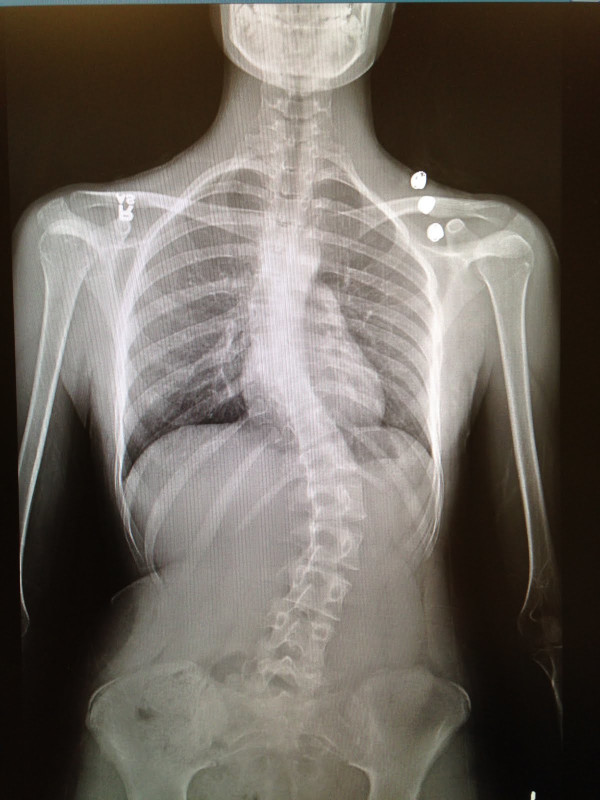

Scoliosi

- Descrizione: Deviazione laterale della Colonna vertebrale a forma di S o C.